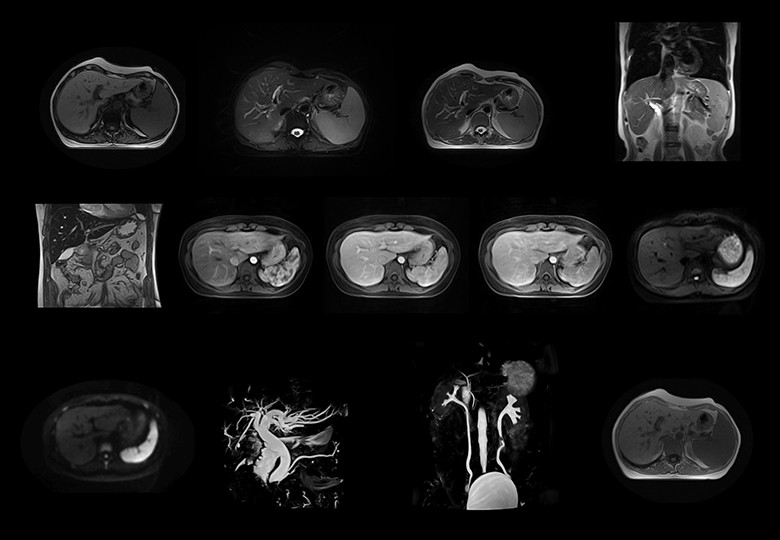

• Abdomen

• Angio+Hydro